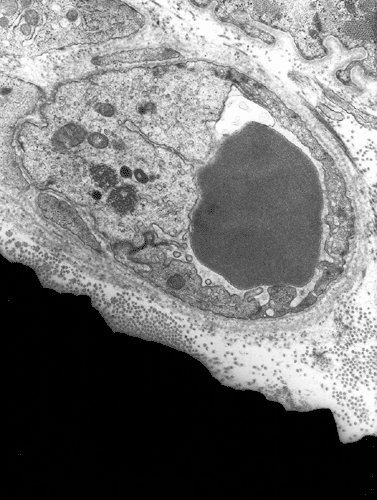

Diagnostic procedure

A biopsy was performed. The followings are representative photomicrographs of the biopsy material.

Pathology of the case:

| G. | H. | I. | J. |

What is your diagnosis? Discussion